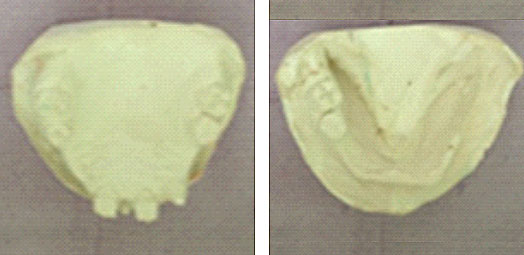

Sur le moulage issu de l’empreinte mandibulaire (Fig.7), un porte empreinte individuel en résine chémopolymérisable a été réalisé, ajusté au niveau osté-muqueux et espacé avec de la cire au niveau des dents (Fig.8). Après ajustage du porte empreinte individuel (Fig.9) et réalisation du joint périphérique (Fig.10) ; l’empreinte secondaire est réalisée à l’aide d’un élastomère fluide (Fig.11) puis coulée au laboratoire (Fig.12).